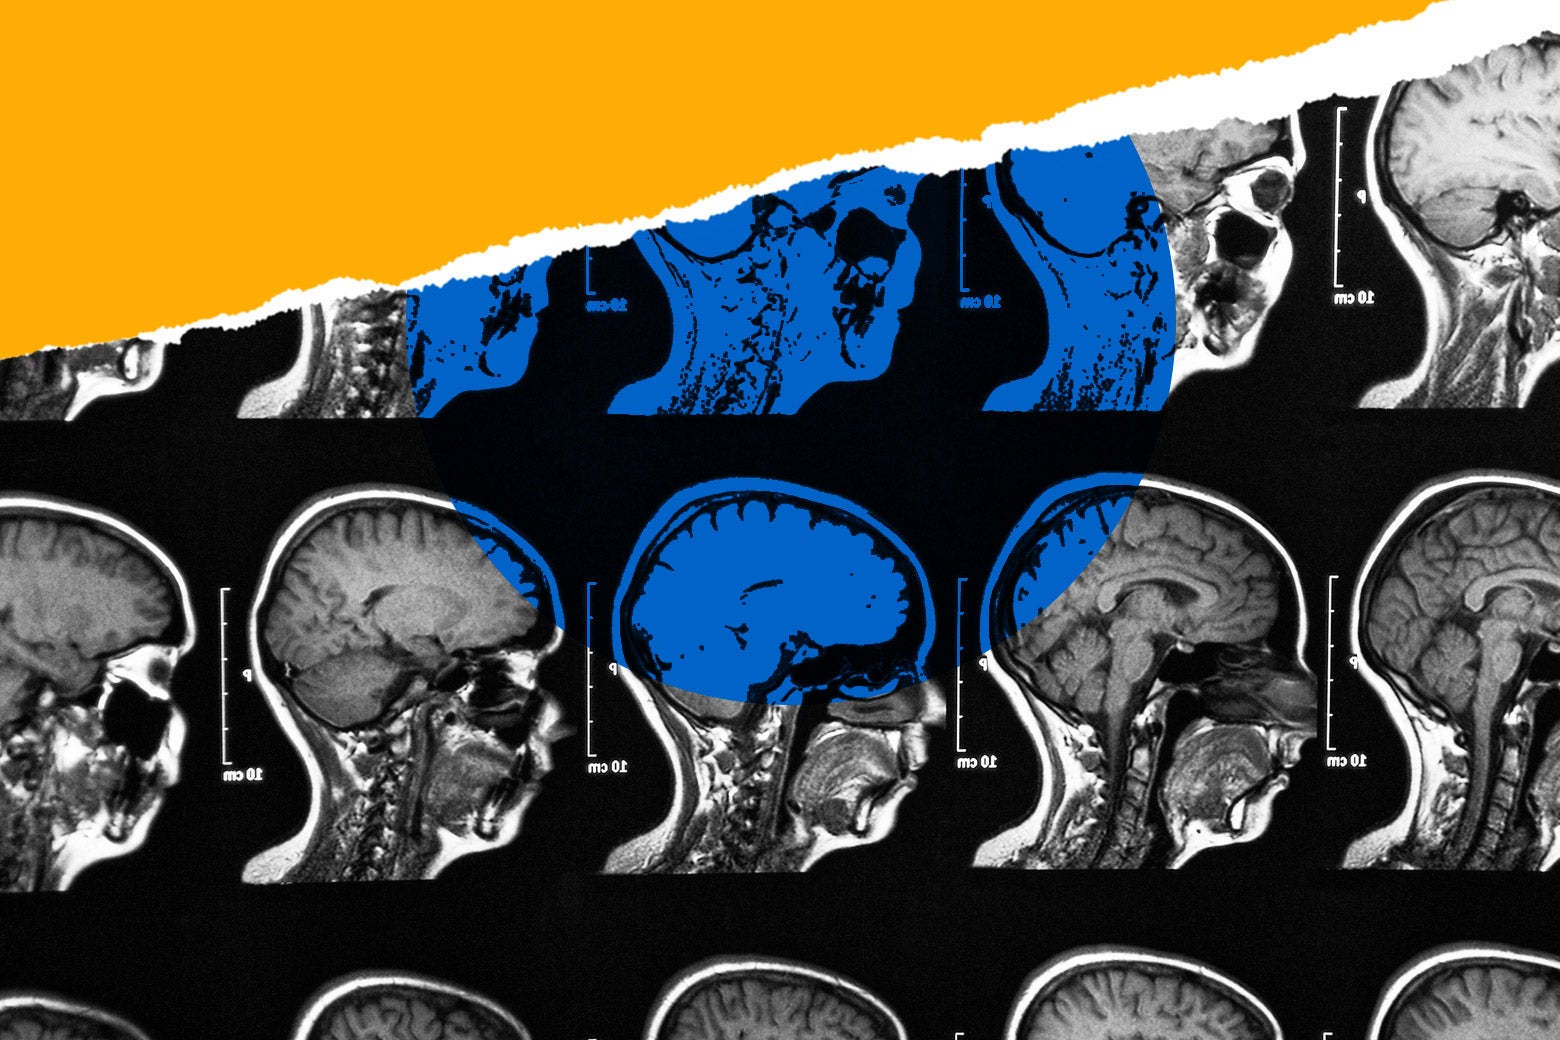

Finally We wish PressBee provided you with enough information of ( Is a 25-Year-Old’s Brain Mature? )